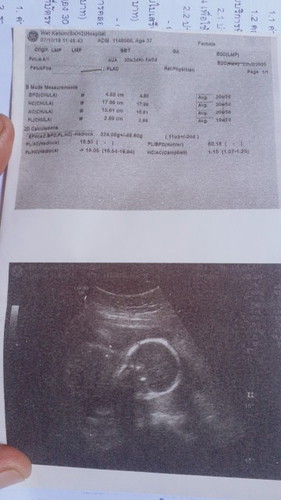

เพิ่งซาวมาวันนี้ แม่ๆช่วยดูทีว่าภาพนี้น้องดขานอนคว่ำรึหงาย หมอบอก 20 สัปดา 2 วัน ตามเครื่องซาวบอกเลยค่ะ กำหนดคลอด 22/2/63 มองภาพทีไรก็เหมือนจะคว่ำ

มองเห็นคว่ำค่ะ